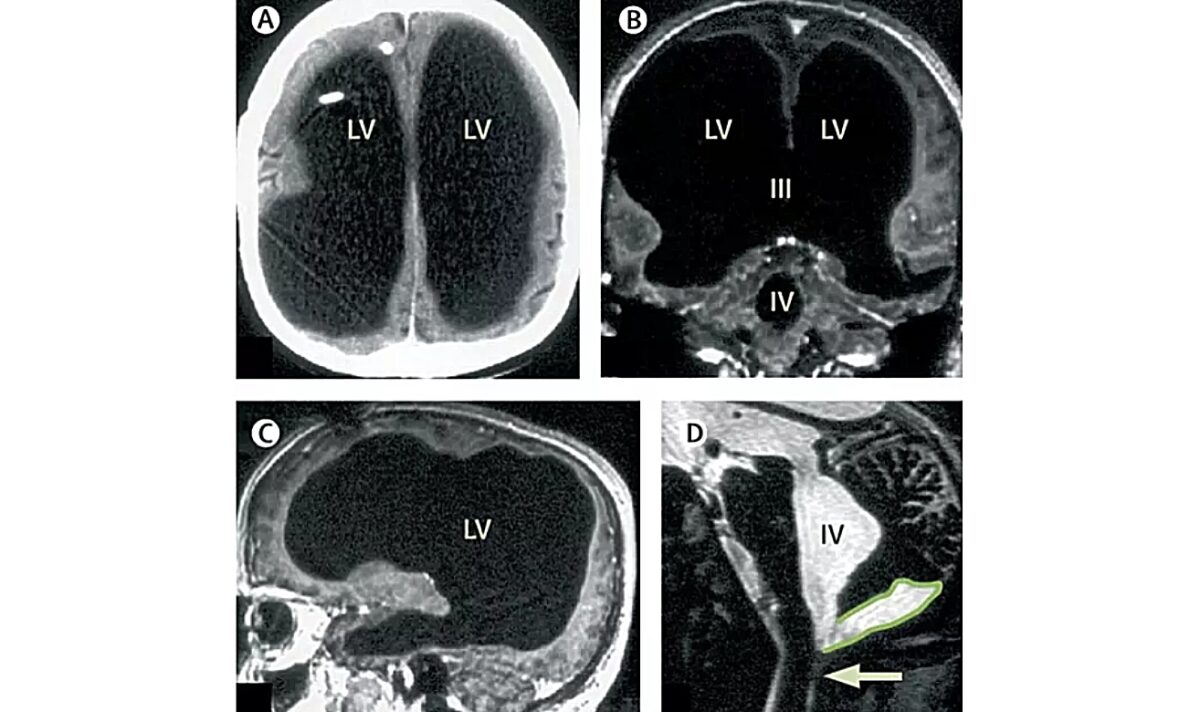

Κατά τη διάρκεια μιας μαγνητικής τομογραφίας (MRI), οι απεικονίσεις έδειξαν ότι το μεγαλύτερο μέρος του κρανίου του άντρα ήταν γεμάτο με υγρό, αντί για εγκεφαλικό ιστό.

Ενώ αρχικά θεωρήθηκε ότι ο ιστός του εγκεφάλου είχε διαβρωθεί, οι επιστήμονες πλέον πιστεύουν ότι συμπιέστηκε από το υγρό. Ο εγκεφαλικός ιστός είχε συμπιεστεί σε ένα λεπτό εξωτερικό στρώμα κατά μήκος των άκρων του κρανίου του, αφήνοντας το 90% του κρανίου γεμάτο με υγρό αντί για εγκεφαλική ουσία.

Η κατάσταση αυτή οφείλεται σε υδροκεφαλία, μια διαταραχή που περιλαμβάνει τη συσσώρευση υγρού στον εγκέφαλο.

Είχε λάβει θεραπεία για την πάθηση αυτή όταν ήταν παιδί, με την τοποθέτηση βαλβίδας (shunt) για την αποστράγγιση του υγρού. Η βαλβίδα αφαιρέθηκε όταν ήταν 14 ετών.

Με τον καιρό, το υγρό συσσωρεύτηκε ξανά και φαινομενικά συμπίεσε τον εγκεφαλικό του ιστό. Οι νευρολόγοι στη Γαλλία εκπλήσσονται από το πόσο καλά λειτουργεί ο άντρας, δεδομένου του πόσο λίγος εγκεφαλικός ιστός παραμένει άθικτος.